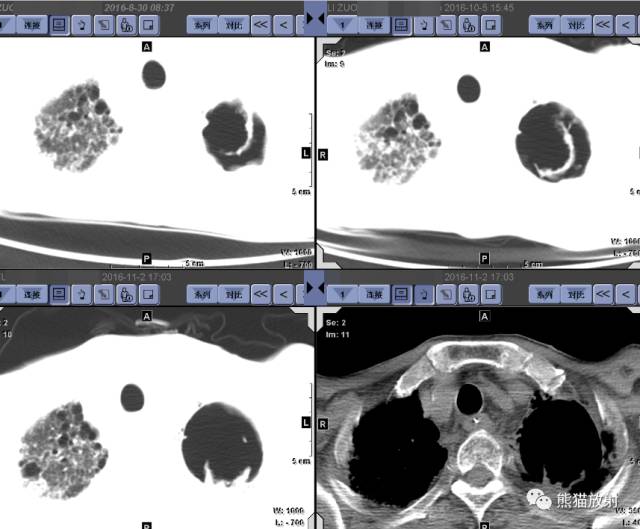

第三例:

男,76岁,下咽癌术后并放疗后;咳嗽、咳痰、憋喘6月余,加重伴发热1月余。痰培养为近平滑念珠菌(真菌)。 医学百科网 | YxBaike.Com

三幅CT肺窗图像的日期(8.30-10.5-11.2),可见空洞逐渐增大,洞内容物脱落、移位,洞壁逐渐变薄。肺间质纤维化表现。

空洞内有内容物(具有活动性) 医学百科网 | YxBaike.Com